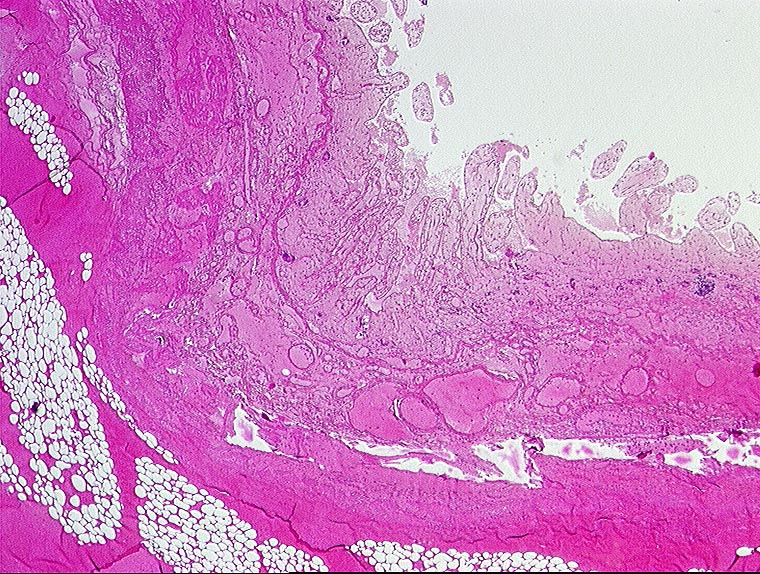

Mesenterialinfarkt

vaskulär / Durchblutungsstörung

Dünndarm

Makroskopie

Pathologischer Befund

Normalbefund